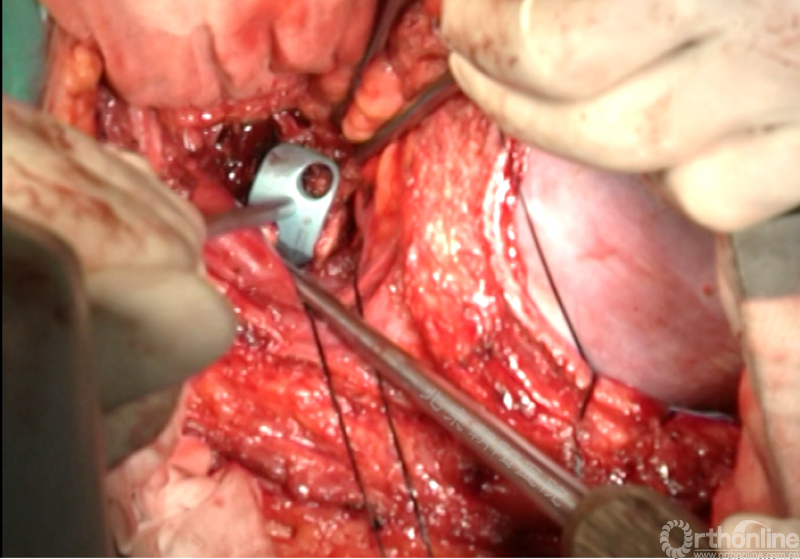

椎间融合器经前方置入凹侧,确保腰椎前凸的恢复和冠状面畸形的矫正,将剩下的骨移植物置入椎间隙内。

置入腹侧金属棒。

使用双棒系统时先安装背侧的棒,可进行90°的去旋转,也可以直接通过前方螺钉矫正冠状面和矢状面的畸形,然后固定后方的棒,可进一步通过加压矫正冠状面畸形。

矫正后神经检测未见异常术中唤醒患者下肢活动良好,术中透视矫正效果满意、内固定位置良好。根据手术具体情况放置合适尺寸的横连接加强内固定。